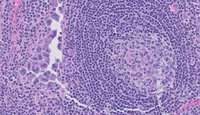

Figure 1: H&E Low Power in Extracavitary Primary Effusion Lymphoma

Low power image (whole slide scan) depicted on the left side shows a lymph node with thin capsule and relatively well-preserved architecture.  At higher power, depicted on the right side, there are scattered regressed secondary lymphoid follicles with some areas of capsular thickening.